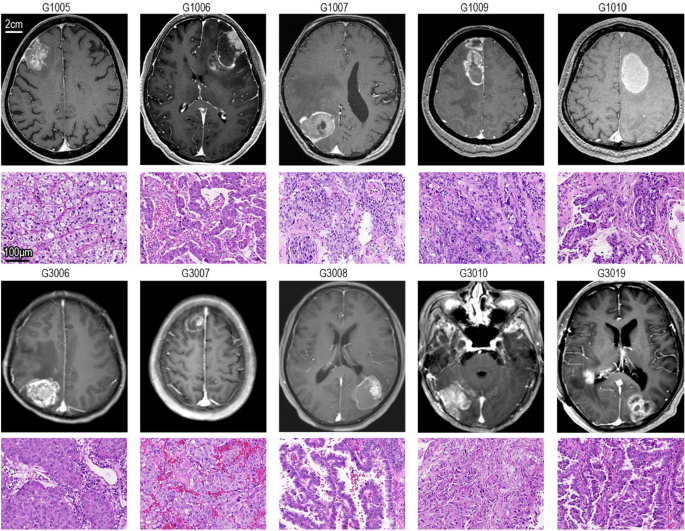

MR and HE staining

The MR images and HE staining images of the tissue samples are shown in Fig. 1. The post-GKRS group samples were labelled G1005, G1006, G1007, G1009, and G1010. The no-GKRS group samples were labelled G3006, G3007, G3008, G3010, and G3019. Mixed signals, which indicated malignant neoplasms, were shown by gadolinium-enhanced MR for all patients. Low signal intensity around the BMs, which indicated edema, appeared in all cases to varying degrees. HE staining indicated that these tissues were metastatic adenocarcinomas.

MR images and HE staining images. The post-γ group consisted of G1005, G1006, G1007, G1009, and G1010. The no-γ group consisted of G3006, G3007, G3008, G3010, and G3019. The MR images with the largest neoplastic diameter were selected. HE staining images are also shown under the MR images for every case.